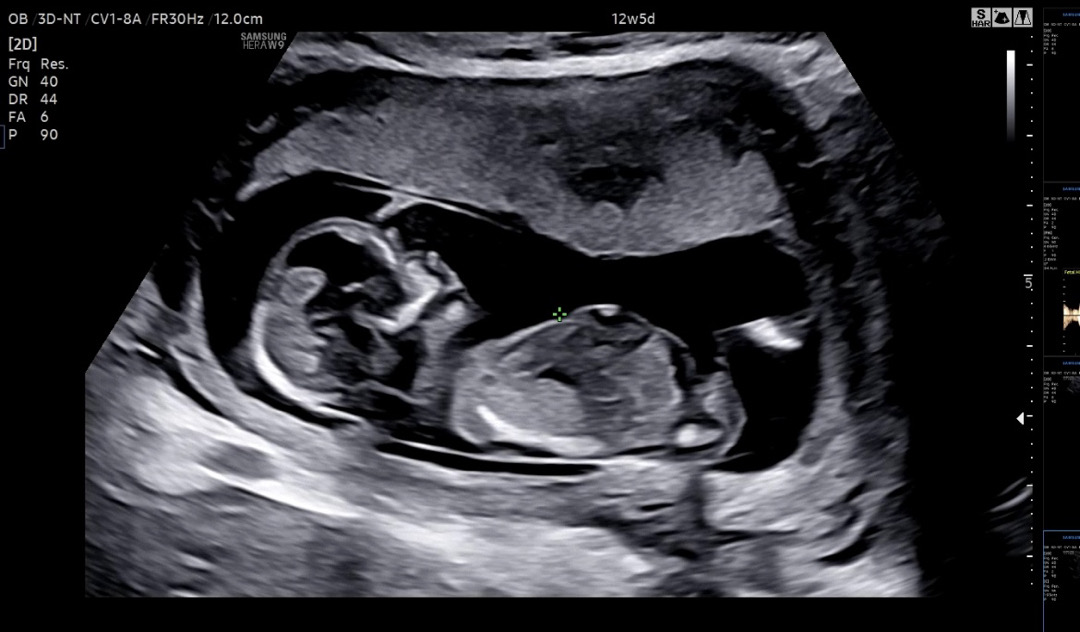

12주4일 각도법 어떻게 보이나요??

궁금하네요